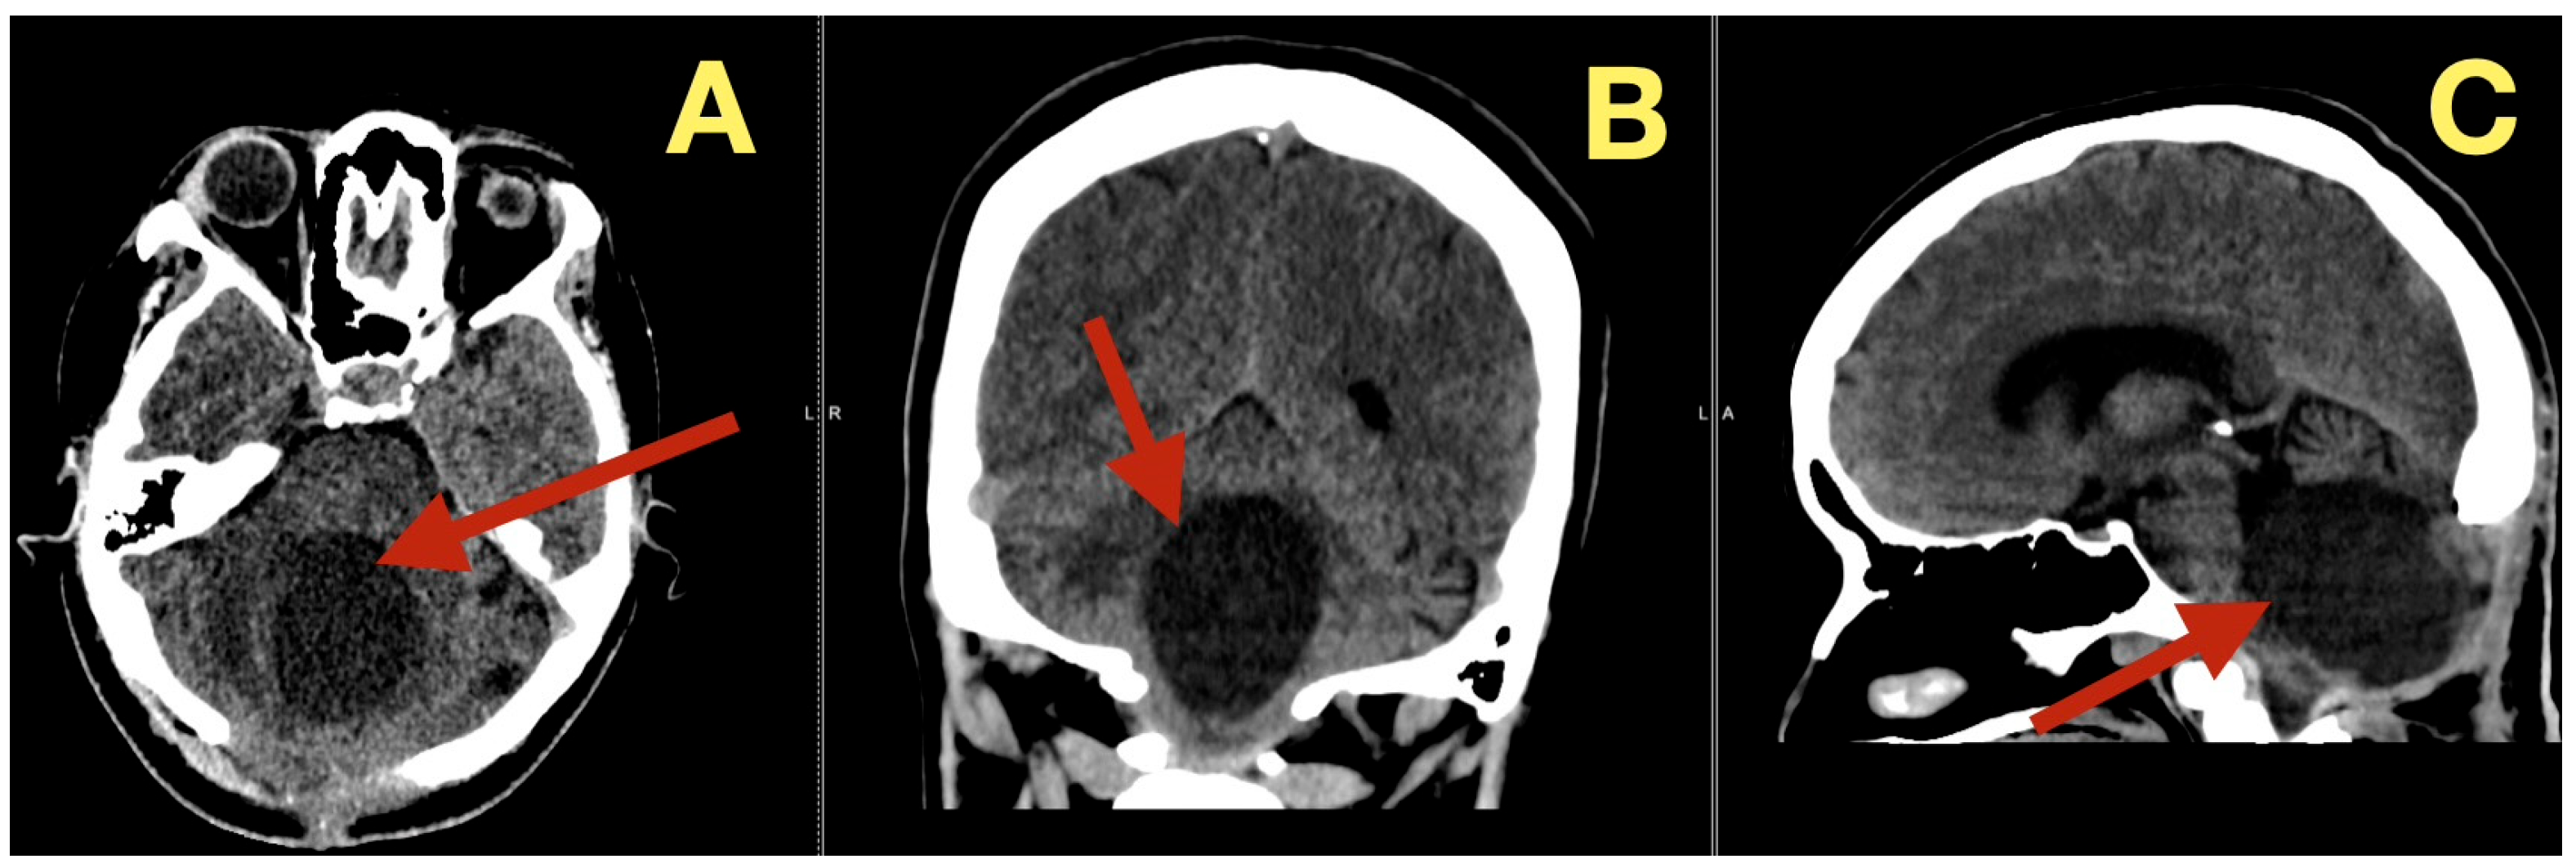

CT scans completed on the first post-operative day (Figure 3) were utilized to exclude hemorrhage and assess early ventricular diameter; they indicated posterior fossa re-expansion, full reopening of the fourth ventricle, normal brainstem convexity, and no early hydrocephalus. A second CT scan completed 7 days post-operatively (Figure 4) verified stable ventricular and outlet patency and excluded late onset hydrocephalus. The one month follow-up CT scan (Figure 5) provided a baseline for long-term comparisons. Later surveillance relied upon MRI including DWI to exclude diffusion-positive residual or recurrence.

Figure 4. One-week postoperative CT scan. (A): Axial CT demonstrating a clean surgical cavity with complete re-expansion of the fourth ventricle and normal CSF flow through the foramen of Magendie (arrow). (B): Coronal CT showing preserved midline symmetry and restored perimedullary cisterns without evidence of fluid collection or residual density (arrow). (C): Sagittal CT confirming normalization of posterior-fossa configuration, intact vermian curvature, and patent foramina of Luschka (arrow).